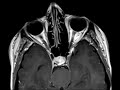

Pituitary Microadenoma

These images show a T1 slightly hypointense, hypoenhancing mass in the posterior right aspect of the pituitary gland, best seen on the sagittal and axial T1 post contrast images. There is no evidence of cavernous sinus invasion. Findings are most compatible with a pituitary microadenoma in this patient with hyperprolactinemia. Differential considerations would include a rathke cleft cyst. Prolactinoma is the most common functional adenoma of the pituitary. In general, microadenomas enhance more slowly than normal pituitary tissue and dynamic post-contrast imaging can be very helpful in identifying subcentimeter lesions.